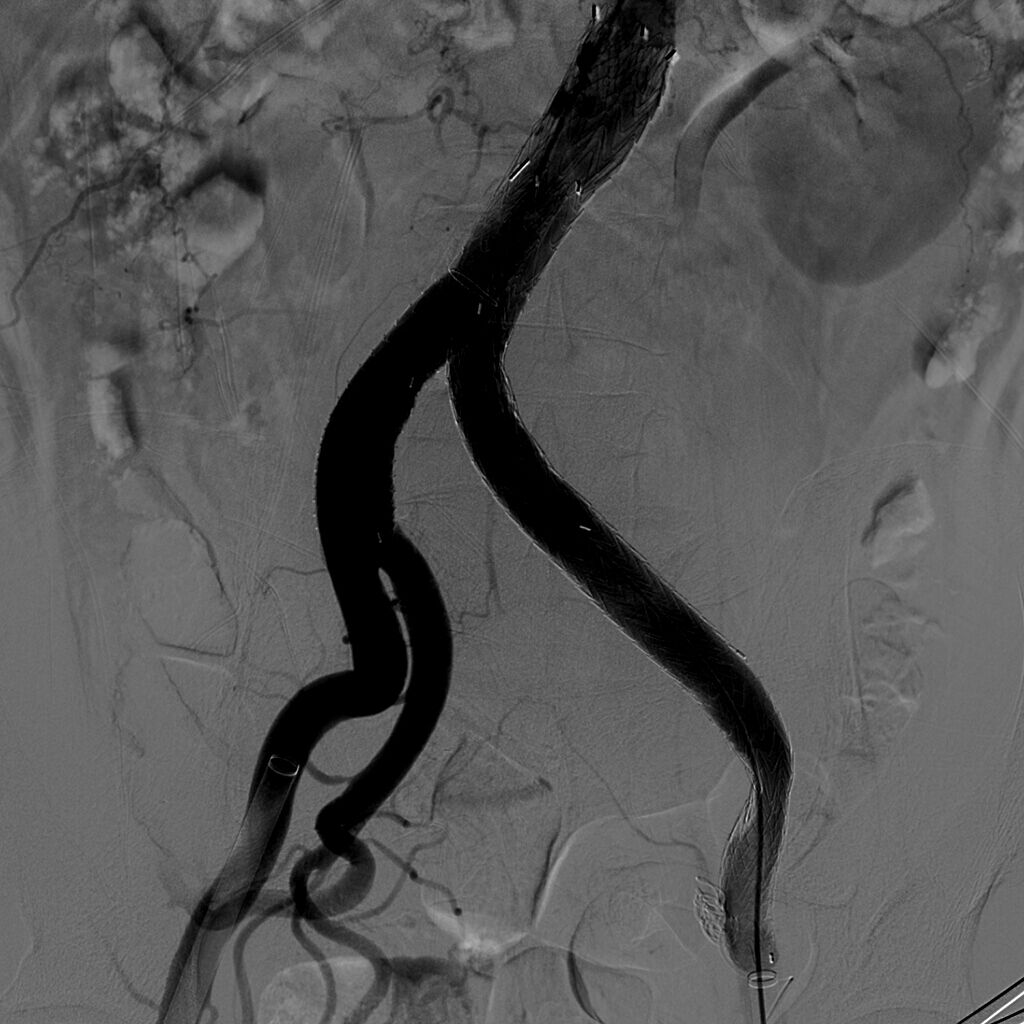

2015年1月15日我院普通外科血管专业组贾玉龙主任医师、汪岩副主任医师及汪鑫住院医师等成功为一巨大髂动脉瘤患者完成了微创手术治疗。患者男性,56岁,承德人,发现下腹部搏动性包块并有疼痛感,于当地医院就诊发现左髂总动脉巨大动脉瘤,当地医院无法治疗此病,遂来我院就诊,经检查发现其左髂总动脉有约10X6X6cm3巨大动脉瘤。

髂动脉扩张性病变直径至少较正常动脉扩大50%即可谓髂动脉瘤,髂总动脉扩张性病变直径大于1.5cm即可称髂总动脉瘤。临床上所见的髂动脉瘤大多数是延续于腹主动脉瘤,位于髂动脉部位包括髂总、髂外和髂内动脉的动脉瘤,而不伴有腹主动脉瘤,称为孤立性髂动脉瘤,临床少见。此例如此巨大,更为罕见。孤立性髂动脉瘤的常见发病部位是髂总动脉和髂内动脉,髂外动脉少见。孤立性髂动脉瘤可以是单发,也可以是多发。动脉瘤破裂出血是孤立性髂动脉瘤高病死率的主要原因,一旦破裂,死亡率高达50%-70%,总体上破裂发生率为14%-70%。通常认为瘤体直径大于3cm破裂风险明显增加,需要手术处理,本例瘤体直径接近7cm。动脉粥样硬化是中、老年人动脉组织结构退行性病变,一旦瘤体形成,只会增大而不会缩小。随着瘤体的增大,可压迫周围组织器官或发生瘤体破裂,目前尚缺乏有效的药物来抑制动脉瘤自然增长、增大的病理过程,也无确切的方法来评估动脉瘤多大以及何时会发生破裂。一旦发现,建议手术治疗。(普外血管组 汪岩)